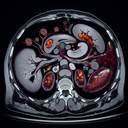

МРТ органів черевної порожнини

Магнітно-резонансна томографія (МРТ) органів черевної порожнини — це неінвазивний метод візуалізації, що дозволяє отримати деталізовані зображення внутрішніх органів та тканин черевної порожнини. Процедура використовує магнітне поле і радіохвилі для створення зображень, що допомагає лікарям діагностувати різні захворювання. **Переваги МРТ:** - Висока точність та якість зображень...